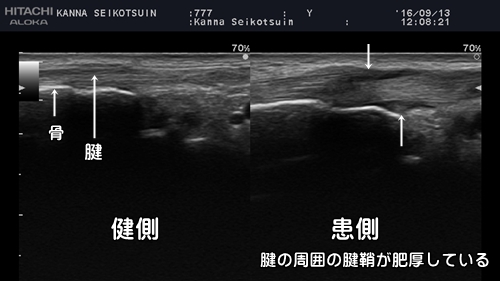

腱鞘炎の超音波エコー画像

当院では腱鞘炎やばね指の患者様にはまず触診や徒手検査で丁寧に診察をおこないます。腱鞘炎が疑われる場合にはエコー検査で確認します。

正常な腱と腱鞘をエコーで観察すると腱は楕円形で腱鞘内の滑液はほとんど見られません。

エコーでは液体は黒く写ります。

腱鞘炎では腱が腫れて楕円形→円形になります。

また腱鞘に炎症が起こり、滑液が溜まる事で腱の周囲が黒く写ります。